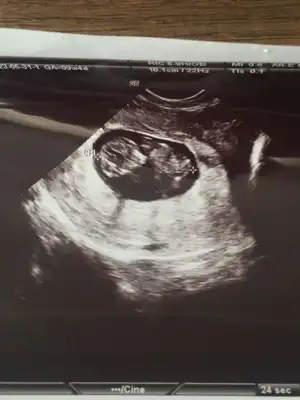

Dün sabah hafif kahverengi lekelenmem olmuştu, gün içinde geçti. Bu sabah da hafif kırmızımsı lekelenme ile uyandım, kahverengiye döndü ama o kadar korktum ki alelacele hastaneye gittik. Hiçbir sıkıntı görünmüyor çok şükür. Miniğim iyiydi.❤️ Nedensiz kanama/lekelenme insan tedirgin oluyor. Zaten progestan kullanıyordum, devam dedi. Merdiven inip çıkmayı bile yasakladı doktorum, hiçbir şey yapmadan istirahat verdi. Çay yasak, kahve yasak. Çok istersem haftada bir fincan Türk kahvesi ancak. Temmuz başında memlekete gitmek istiyordum, şu anki durumla o bile yasak. Geldim progestanımı yaptım yatıyorum.

• IMG-20230531-WA0004.webp

IMG-20230531-WA0004.webp

29,2 KB · Görüntüleme: 68